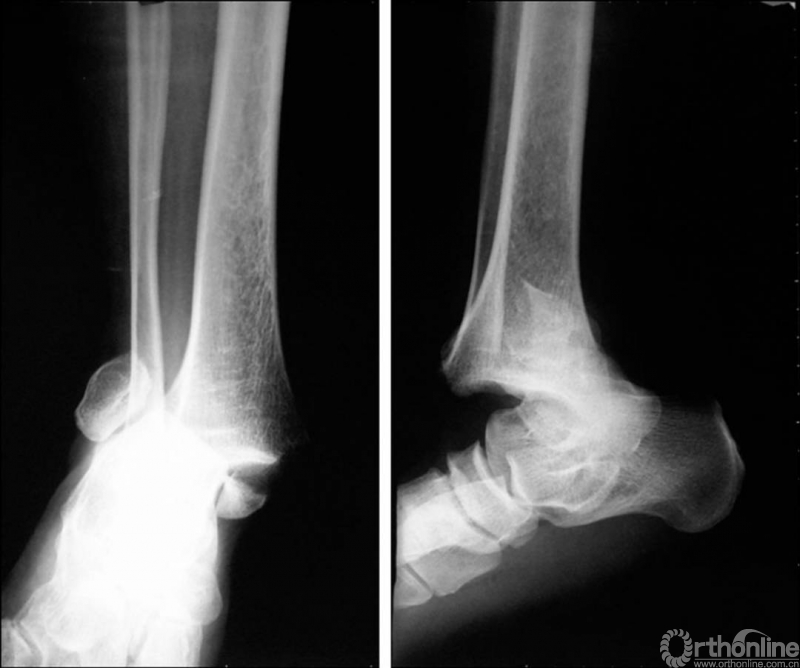

X线诊断:标准的踝关节影像学评估应包括3个位相:前后位(图5),踝穴位(内旋15°)(图6),侧位(图7)。

图5 前后位

图6 踝穴位(内旋15°)

当踝关节严重损伤时内外踝及距骨将发生不同程度的移位(图8)。有时外踝骨折会伴有三角韧带的损伤,静态的X线摄片并不能准确地反映踝关节的稳定性,应力位片及MRI检查可完善对踝关节稳定性及韧带损伤的评估(图9)。此时应通过患肢损伤机制及放射资料准确判断踝关节损伤的类型以正确指导复位和固定。有时单纯内踝骨折可能是更为复杂的“Maisonneuve骨折”的一部分,该骨折还包括腓骨近端骨折及韧带联合损伤,故X线检查应投照整个胫腓骨。

图8 骨折移位明显合并有脱位